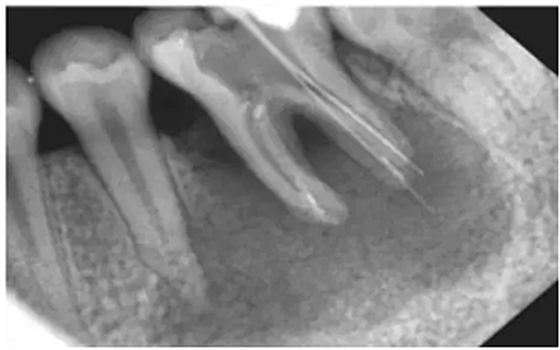

注:a.在鈣化細(xì)小/彎曲/形成臺(tái)階的根管,即使銼針未到狹窄區(qū),阻力也會(huì)明顯增大,導(dǎo)致感覺錯(cuò)誤;b.在根尖周組織破壞嚴(yán)重(陰影部分),有痛感時(shí),已明顯超出根管口。(如圖)

方法二:X光

采用X光拍片測量

優(yōu)點(diǎn):能觀察牙的全貌,尤其是牙冠和牙根的解剖形態(tài),冠根關(guān)系以及牙根的大小、形態(tài)和位置

缺點(diǎn):操作繁瑣、費(fèi)事、射線污染

1) 三維結(jié)構(gòu)投射在二維平面上,因投射角度不一樣,數(shù)據(jù)容易出錯(cuò)。

2)根尖孔不能體現(xiàn)在牙片上,而80%以上的根尖孔都不在牙齒根尖而是在側(cè)邊。

根尖開口在側(cè)邊時(shí),X線片投射引起長度偏差錯(cuò)誤。

根尖開口距離牙齒根尖距離越大,誤差越大,會(huì)引起嚴(yán)重超充。